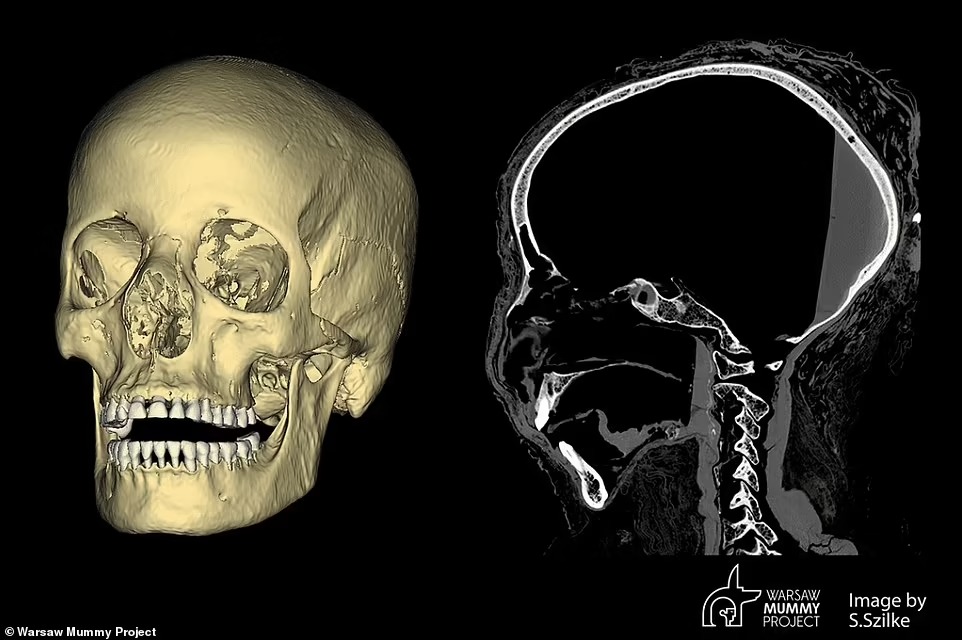

ووفقًا لصحيفة ديلي ميل البريطانية، فإن صاحبة المومياء ماتت بسبب نادر من المرض، حيث مر على حملها نحو 28 أسبوع، وأجرى باحثون من بولندا، مسحًا لجمجمة الجثة للمرأة المصرية القديمة، عندما اكتشفوا علامات غير عادية في العظام.

وتُظهر الصور الصادرة عن مشروع وارسو مومياء WMP في بولندا، أن الجمجمة المصابة بآفات على الأرجح، ناتجة عن ورم وعيوب كبيرة في أجزاء من العظام، لا تتشكل عادةً أثناء إجراءات التحنيط.

وقال الدكتور رافاي ستيك من قسم الأورام بجامعة وارسو الطبية، وقائد البحث: لدينا تغيرات غير عادية في عظام البلعوم الأنفي، مع حدوث تغييرات في ورم بالعظام.